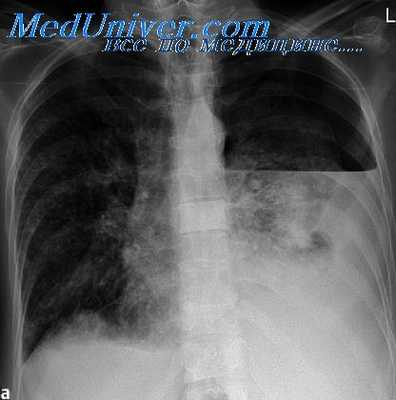

У 57 больных с множественной устойчивостью (HR) преобладала устойчивость еще к 4-5 противотуберкулезным препаратам. При этом наиболее частой формой заболевания был прогрессирующий фиброзно-кавернозный туберкулез, в том числе осложненный эмпиемой плевры, казеозная пневмония, т.е. самые тяжелые поражения легких.

Основным видом операций были резекции легких, они выполнены у 80 больных (пненмоэктомий—14, лобэктомяй — 19, и резекции сегментов у 47). У всех имелись прочные сращения плевральных листков, у 69 из них пришлось легкое выделять экстраплеврально, что увеличивало кровопотерю в среднем до 800 мл. При выделении легкого произошел разрыв каверны у 6 больных, у всех были надрывы легкого из-за эмфиземы и пневмосклероза.

Однако ни в одном случае у больных не наблюдалось положительных рентгено-анатомических сдвигов. Полости распада не уменьшались в размерах, экссудативная реакция вокруг очагов диссеминации не исчезала. Более того степень прогрессирования нарастала на фоне проводимого лечения.